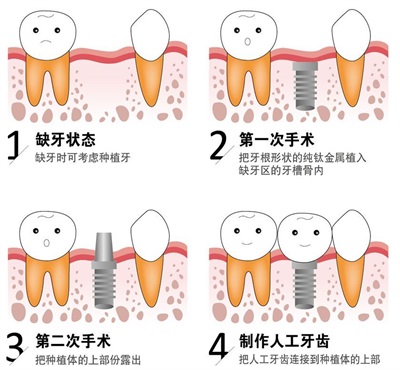

▲种植牙过程示意图

种植牙其实是在缺牙部位的牙槽骨上钻一个小孔,然后在里面安装一个纯钛种植体,待一段时间的愈合期后,再在种植体上安装全瓷牙冠。